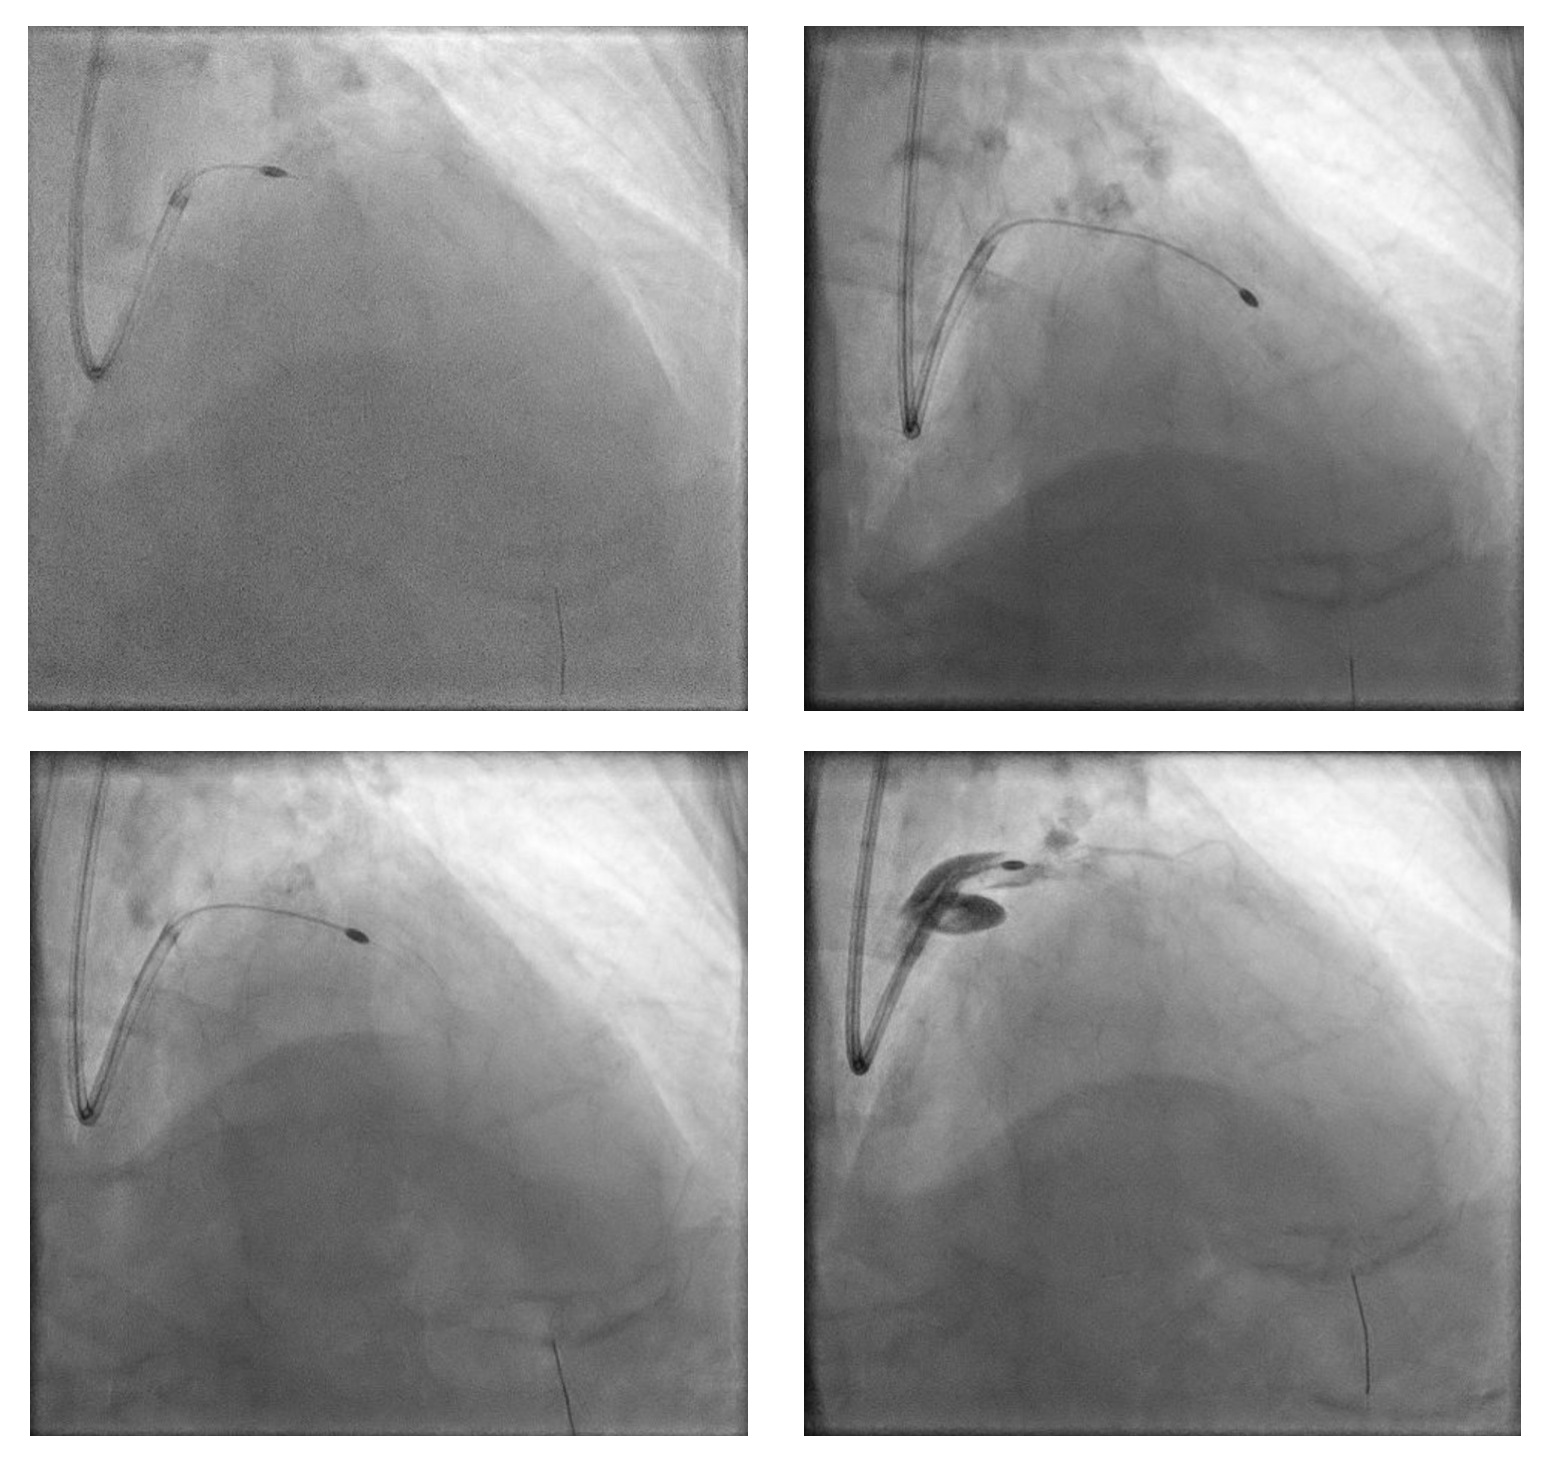

PCI was initiated with Full Dose Heparin. LAD wired with Runthrough NS Floppy; predilatation with 2.0 ¡¿ 15 mm SC balloon. IVUS failed to cross proximal LAD, showing nodular calcium. Rotational atherectomy was performed using Rotapro 1.75 mm burr (180,000 rpm, four runs) followed by one polishing run at 150,000 rpm. Chest pain and ST elevation occurred shortly after rotablation due to Type F dissection in distal LM (TIMI 0 LAD). Bailout stenting with Promus Premier 3.5 ¡¿ 38 mm from LM–LAD was performed using jailed-balloon technique, followed by post-dilatation and IVUS optimization.

A second stent (Promus Premier 2.75 ¡¿ 24 mm) was implanted in proximal–mid LAD overlaping with previous stent, then high-pressure post-dilatation and POT (NC 4.5¡¿8 mm) was performed. LCx was rewired and treated with TAP stenting (Promus Premier 3.5 ¡¿ 18 mm) after sequential and final kissing balloon dilatations. Post-IVUS confirmed well-expanded and well-apposed stents (MSA LAD 5.22 mm©÷; LCx 7.82 mm©÷).